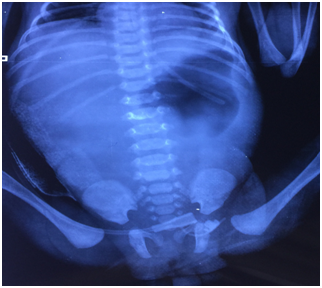

Postoperatively, the baby was kept stable on intravenous fluids and antibiotics were started according to culture reports. The stoma did not function till the 9th postoperative day despite adequate gut stimulation (proximal and distal stomal washes, gavage feeds, rectal washes, prokinetics including metclopramide and erythromycin). The child was maintained on total parentral nutrition (TPN) since repeated attempts on establishing oral feeds were rendered unsuccessful and the child vomited oral feeds. The postoperative X‒ Ray abdomen showed an enlarged gastric shadow suggestive of persistent gastric dilatation and absence of distal gas (Figure 4).

Figure 4 X‒ray abdomen (post operative day 9) showing large gastric shadow with no distal gas suggestive of decreased or absent motility.